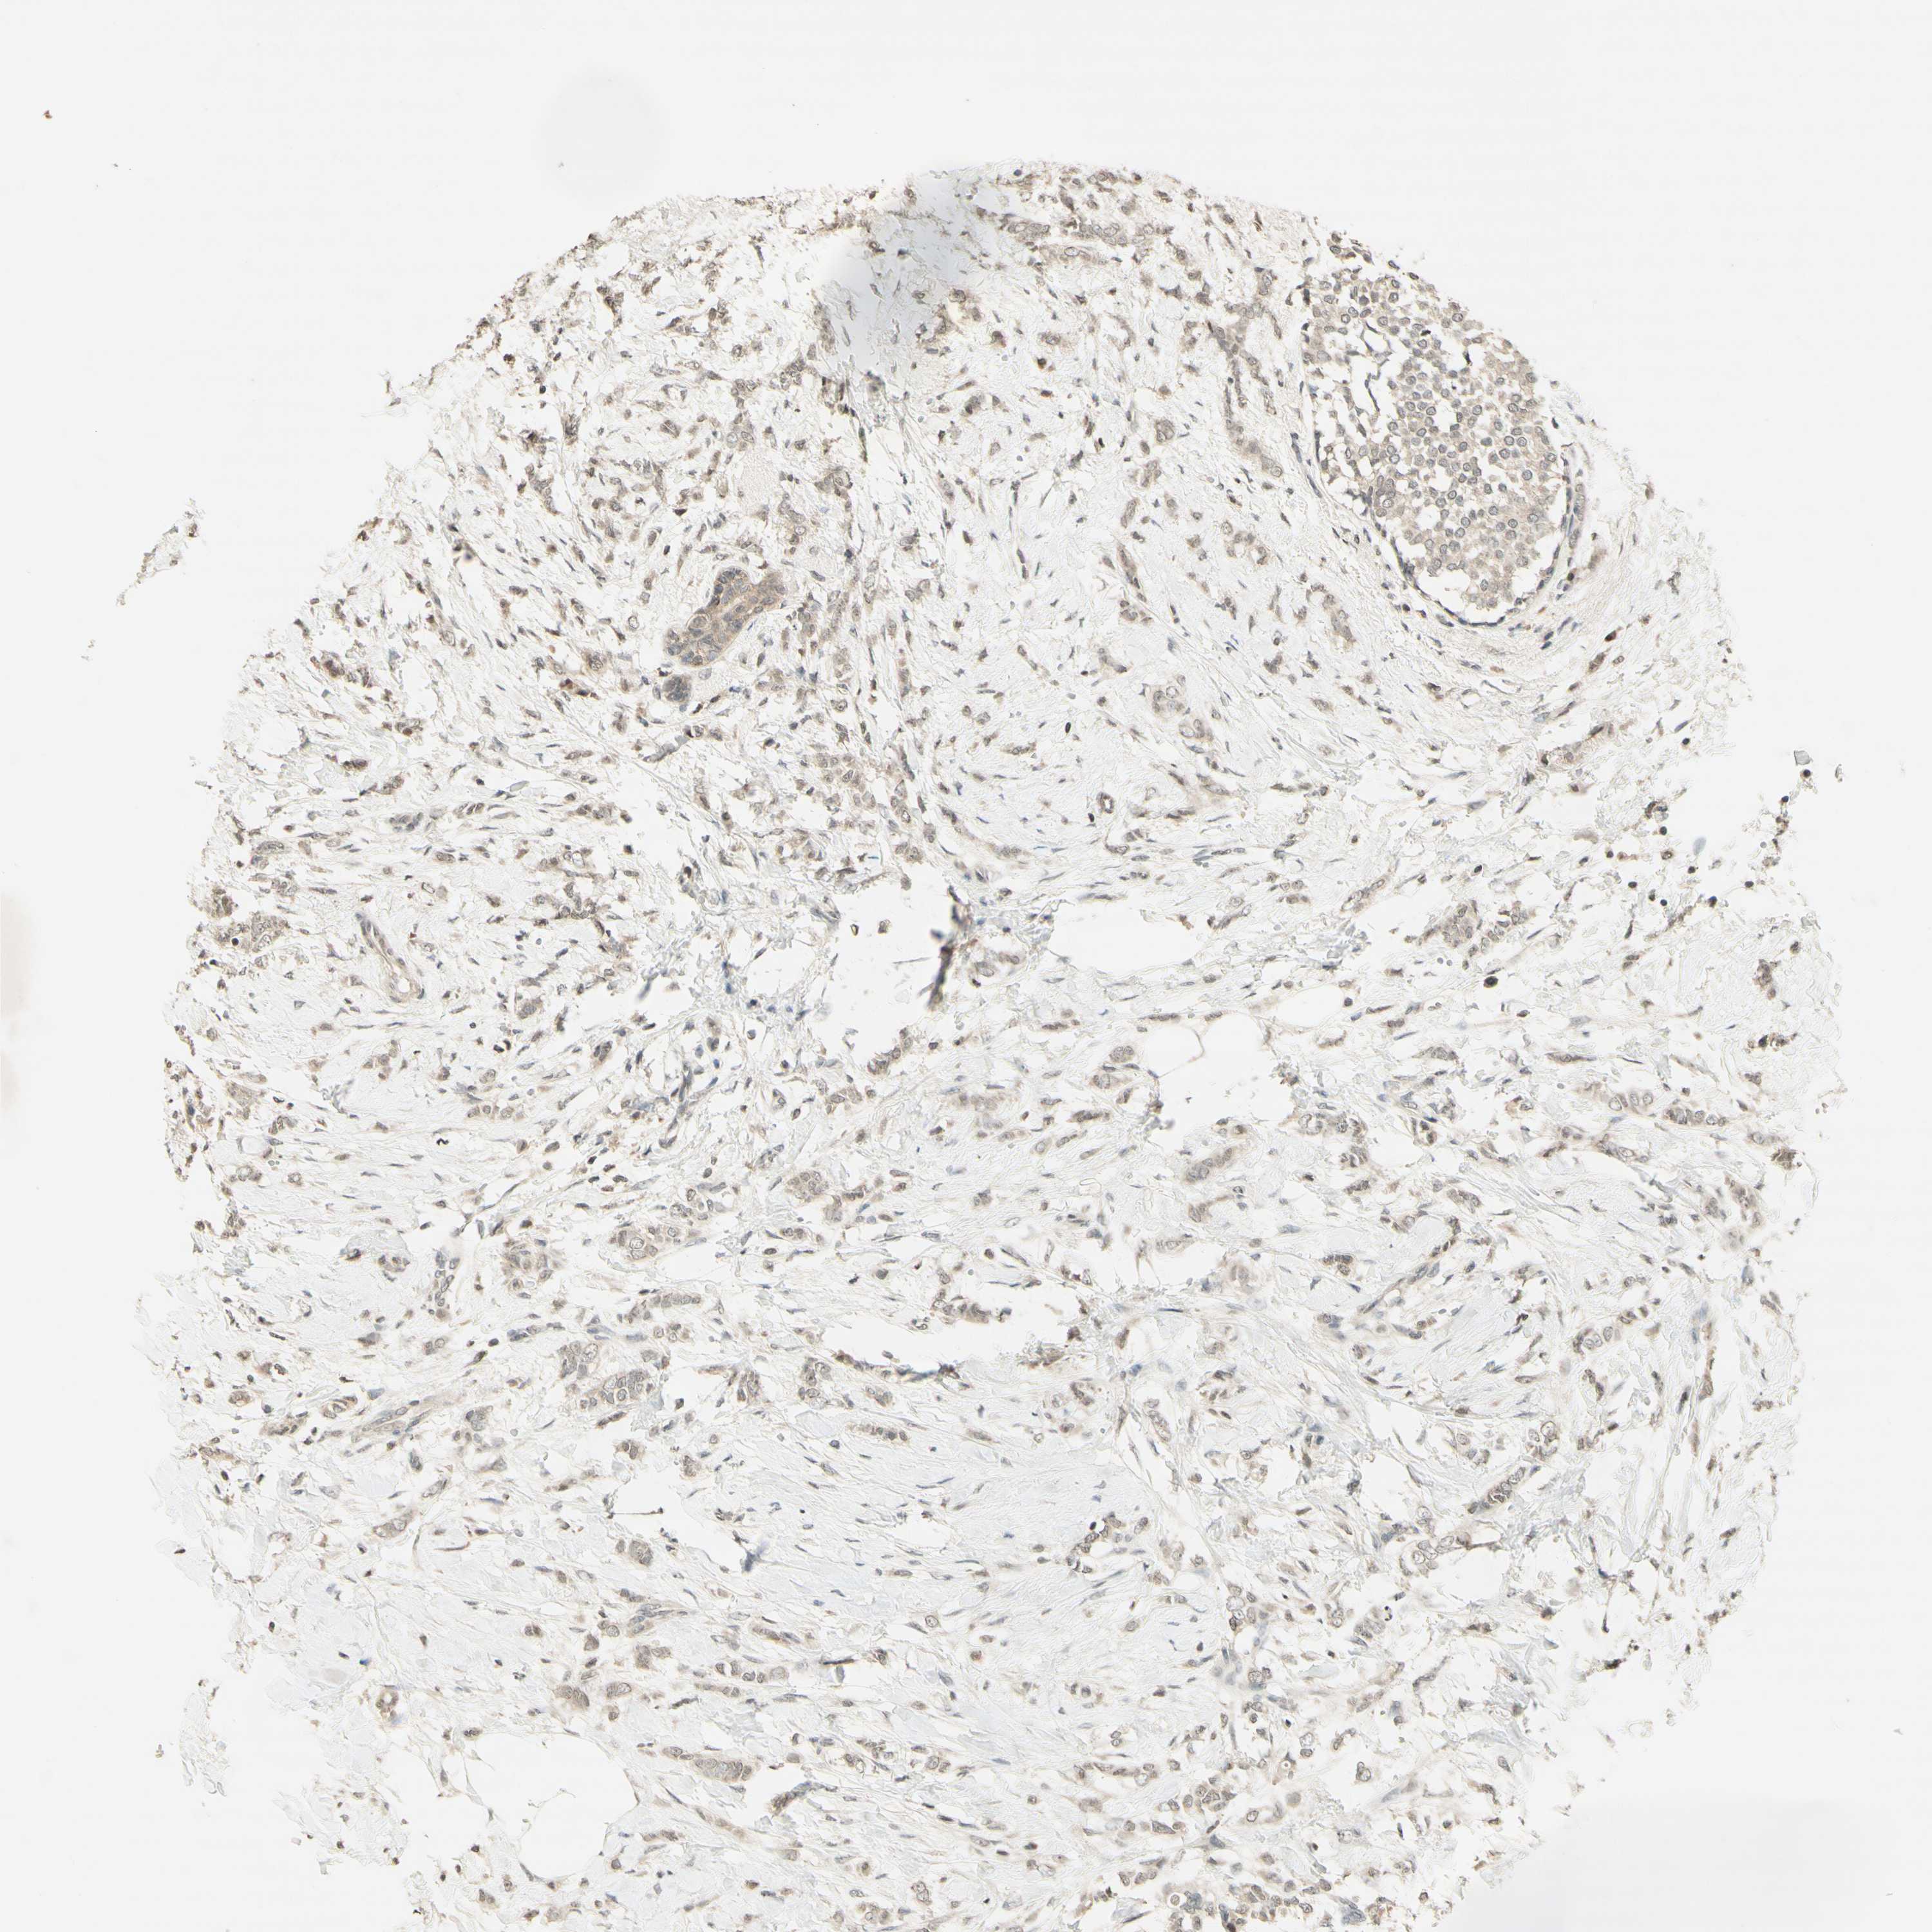

CANCER BREAST CANCER Show tissue menu

BRCA TCGA BRCA VALIDATION PROTEIN EXPRESSION

ANTIBODIES

AND

VALIDATION